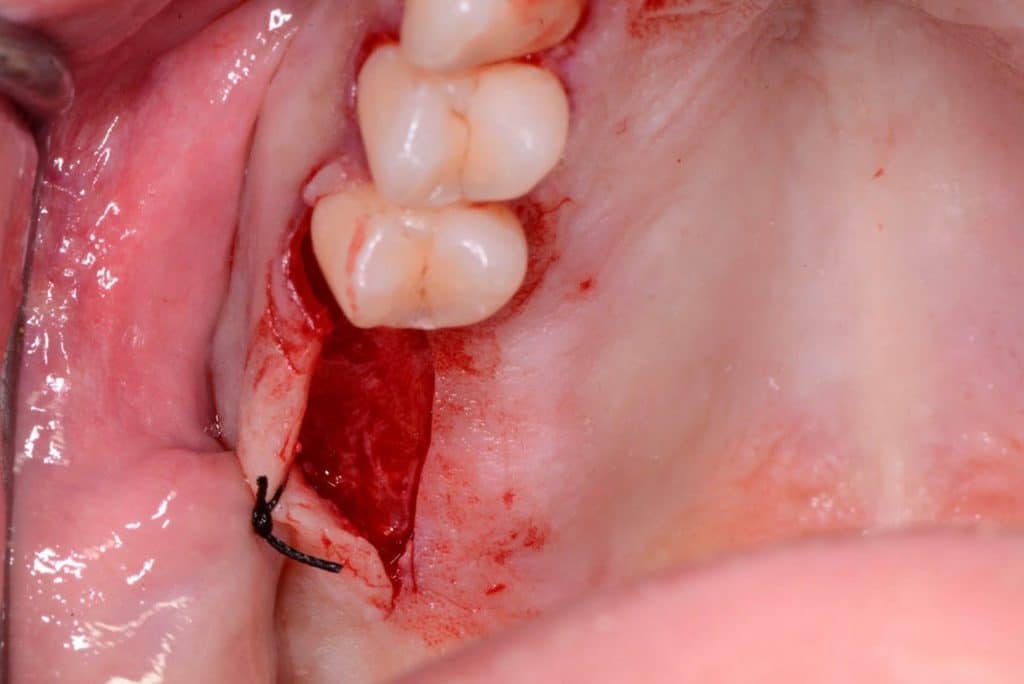

Two 8mm Straumann Wide-Neck have been inserted. After inserting a healing abutment with a height of 2 mm, a detached stitches suture was made. Good planning allowed me to be precise with the incision, and only 2 stitches have been necessary.